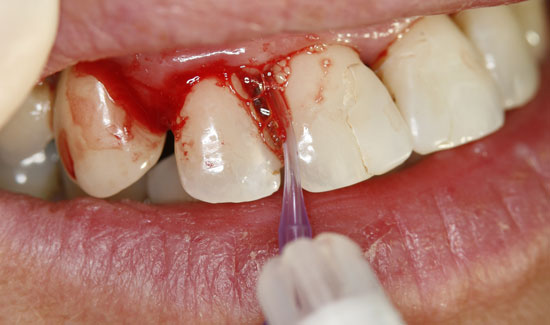

Fig. 2: Clinical aspect of region 12, formation of gas bubbles on the inflamed tissue. Continuous suction in the vicinity of the area of use

As an ozone gas source, we used Prozone, which, with the aid of plastic attachments, makes it possible to introduce ozone gas into the pockets in a pain-free manner. The local application of ozone gas was repeated three times, at weekly intervals. The patient was also made aware of necessary personal hygiene measures. Not only were we able to stop the bleeding, but we were also able to keep the degree of mobility of the teeth at a stable level (2) and reduce the measurable depth of the pockets.